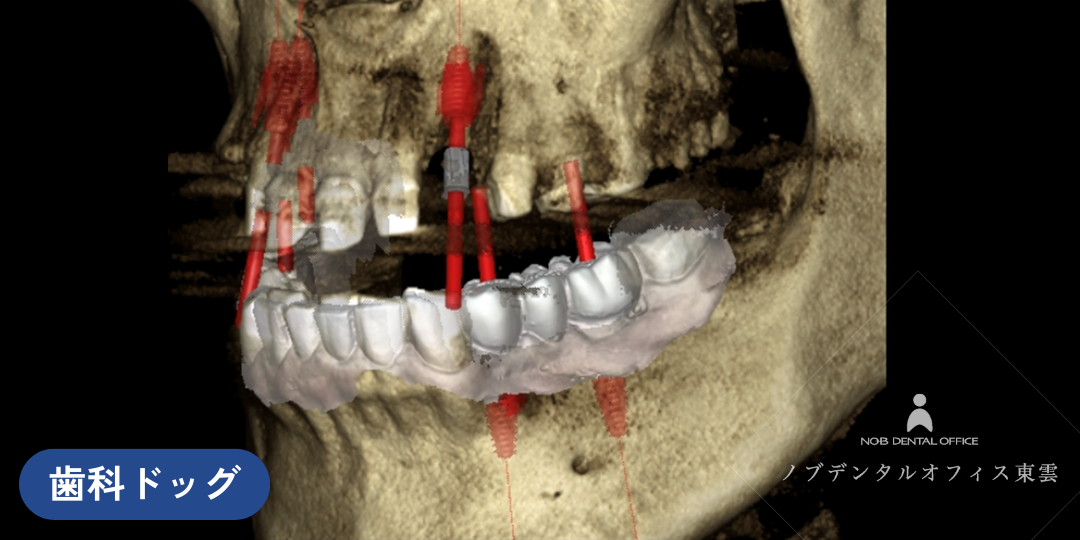

3次元で診査できる歯科用CT

そこで、抜かなければならない箇所はインプラントを行い、噛み合わせを考え、下の前歯を矯正します。

7本のインプラントを入れ、仮歯にて噛み合わせがないか確認を行います。

親知らずを含め、ご自身の保存が難しい10箇所について歯を抜きました。

7本のインプラントをいれた後、仮歯をセットしています。